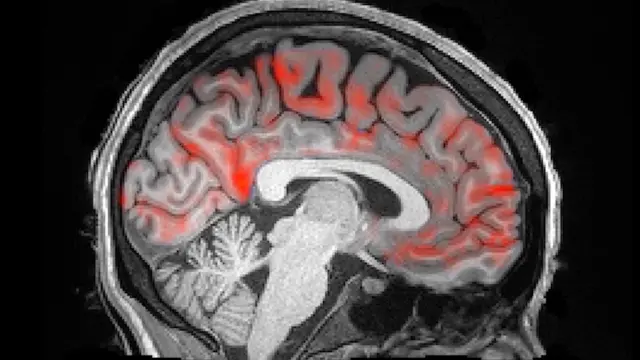

La corteza cerebral está sumergida en líquido cefalorraquídeo acuoso (LCR). Realizando una resonancia magnética mientras dormían a 13 jóvenes de entre 23 y 33 años, se ha descubierto que en algunas fases del sueño se generan unas ondas que mueve el LCR como las olas del mar, lavando el cerebro para eliminar toxinas y proteínas dañinas. Puedes verlo en esta resonancia magnética:

La sangre rica en oxígeno, que en el vídeo se ve de color rojo, se mueve hacia la parte exterior del cerebro, mientras una ola de líquido cefalorraquídeo, de color azul, se mueve desde uno de los ventrículos.